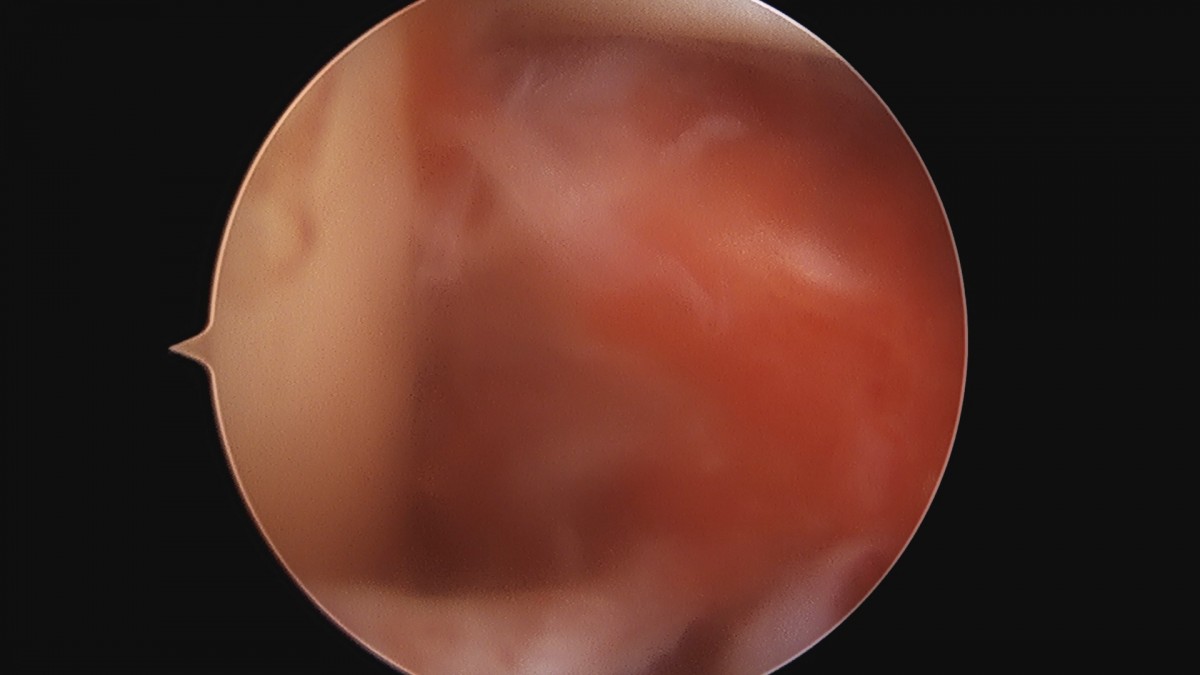

이재상원장님 어깨 견봉하 감압술 김봉O 환자

dae765e4d9ac96aee867c9d6292d8784_1758004119_4142.jpg